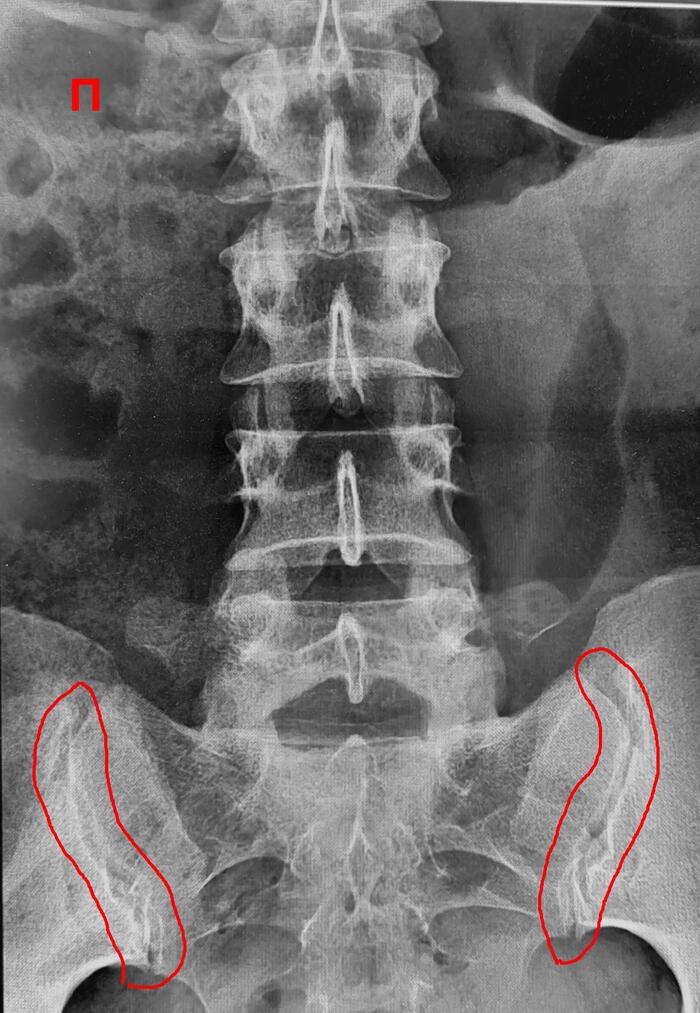

Рентгенограммы поясничного отдела позвоночника пациента с длительным, выраженным болевым синдромом(6 мес.) в пояснице, с временным эффектом от приема НПВС. При описании снимков выраженной костной патологии в поясничном отделе позвоночника не выявлено: структура тел позвонков не изменена, травматических, деструктивных изменений не выявлено, субхондральный склероз замыкательных пластин тел позвонков отсутствует, краевые остеофиты тел позвонков не выявлены, имеется не выраженное неравномерное сужение межпозвонковых щелей как начальное проявления остеохондроза-такая рентгенологическая картина не дает столь выраженного и длительного болевого синдрома.

Обращают на себя внимание крестцово-подвздошные сочленения(КПС),отмечается неравномерное не выраженное сужение щелей КПС с локальными участками расширения, субхондральный склероз- более выраженный слева, имеются двусторонние краевые остеофиты, в нижней трети левого КПС суставная щель не ровная, "изъеденная", по причине наличия единичных эрозий костной ткани. Заключение: Двусторонний сакроилиит 2 ст.(более выраженный слева).